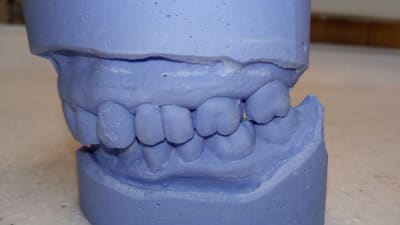

un patient 46 ans de longue date vient me voir pour la casse distale du bridge cantilever maxi gauche, fait sur dent vivante il y a 16 ans, réalisé après de l'ortho, la 14 a été extraite, avec un espace dispo entre 15-13 réduit.

De plus, avec un bilan paro correct,il trouve que les espaces surtout entre 46-47, 16-17 s'agrandissent et lui gênent de plus en plus.

bon bein, niveau ortho c'est pas le top... classe 2 secteur 2/3, limite classe 2 secteur 1/4...supraclusion...

Mais quand meme , on voit sur le haut , des plats d usure de 13 à 22 ET aussi , ce qui est interessant,2petits plats sur les pointes palatines de 17 et 27.

En bas tu t en doutes le pb vient de 33 , bien sur .

Alors , ce que je te demanderais , c est de mettre les modeles en occlusion de traviol ,en appui sur ces faces d usures et de prendre une photo .

Meme 2 pcq il doit y avoir 2 positions possibles .

De face et si possible de derriere montrant l interieur .

Ainsi on verra tres vite l endroit du pb que le patient cherche a eviter.

L ortho a été fait tardivement vers 20 ans pour des raisons esthêtiques. La 24 extraite mais semble t il , l ortho n a pas pu fermé l espace.

Mastication surtout droite pour êviter d abimer son bridge depuis des lustres.

Son guidage droit est plus simple , que le gauche.